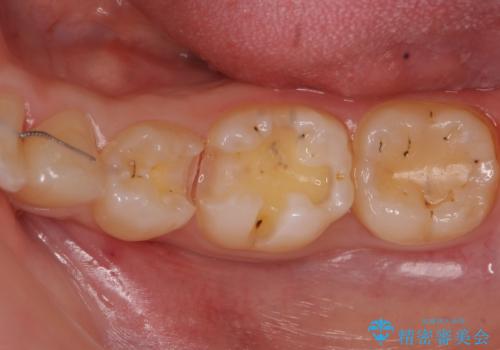

- 奥歯の歯と歯の間が虫歯になっていました。

セラミックインレーで治療しました。

- 14万円 左下56:セラミックインレー7万円×2本費用は治療当時の料金となります